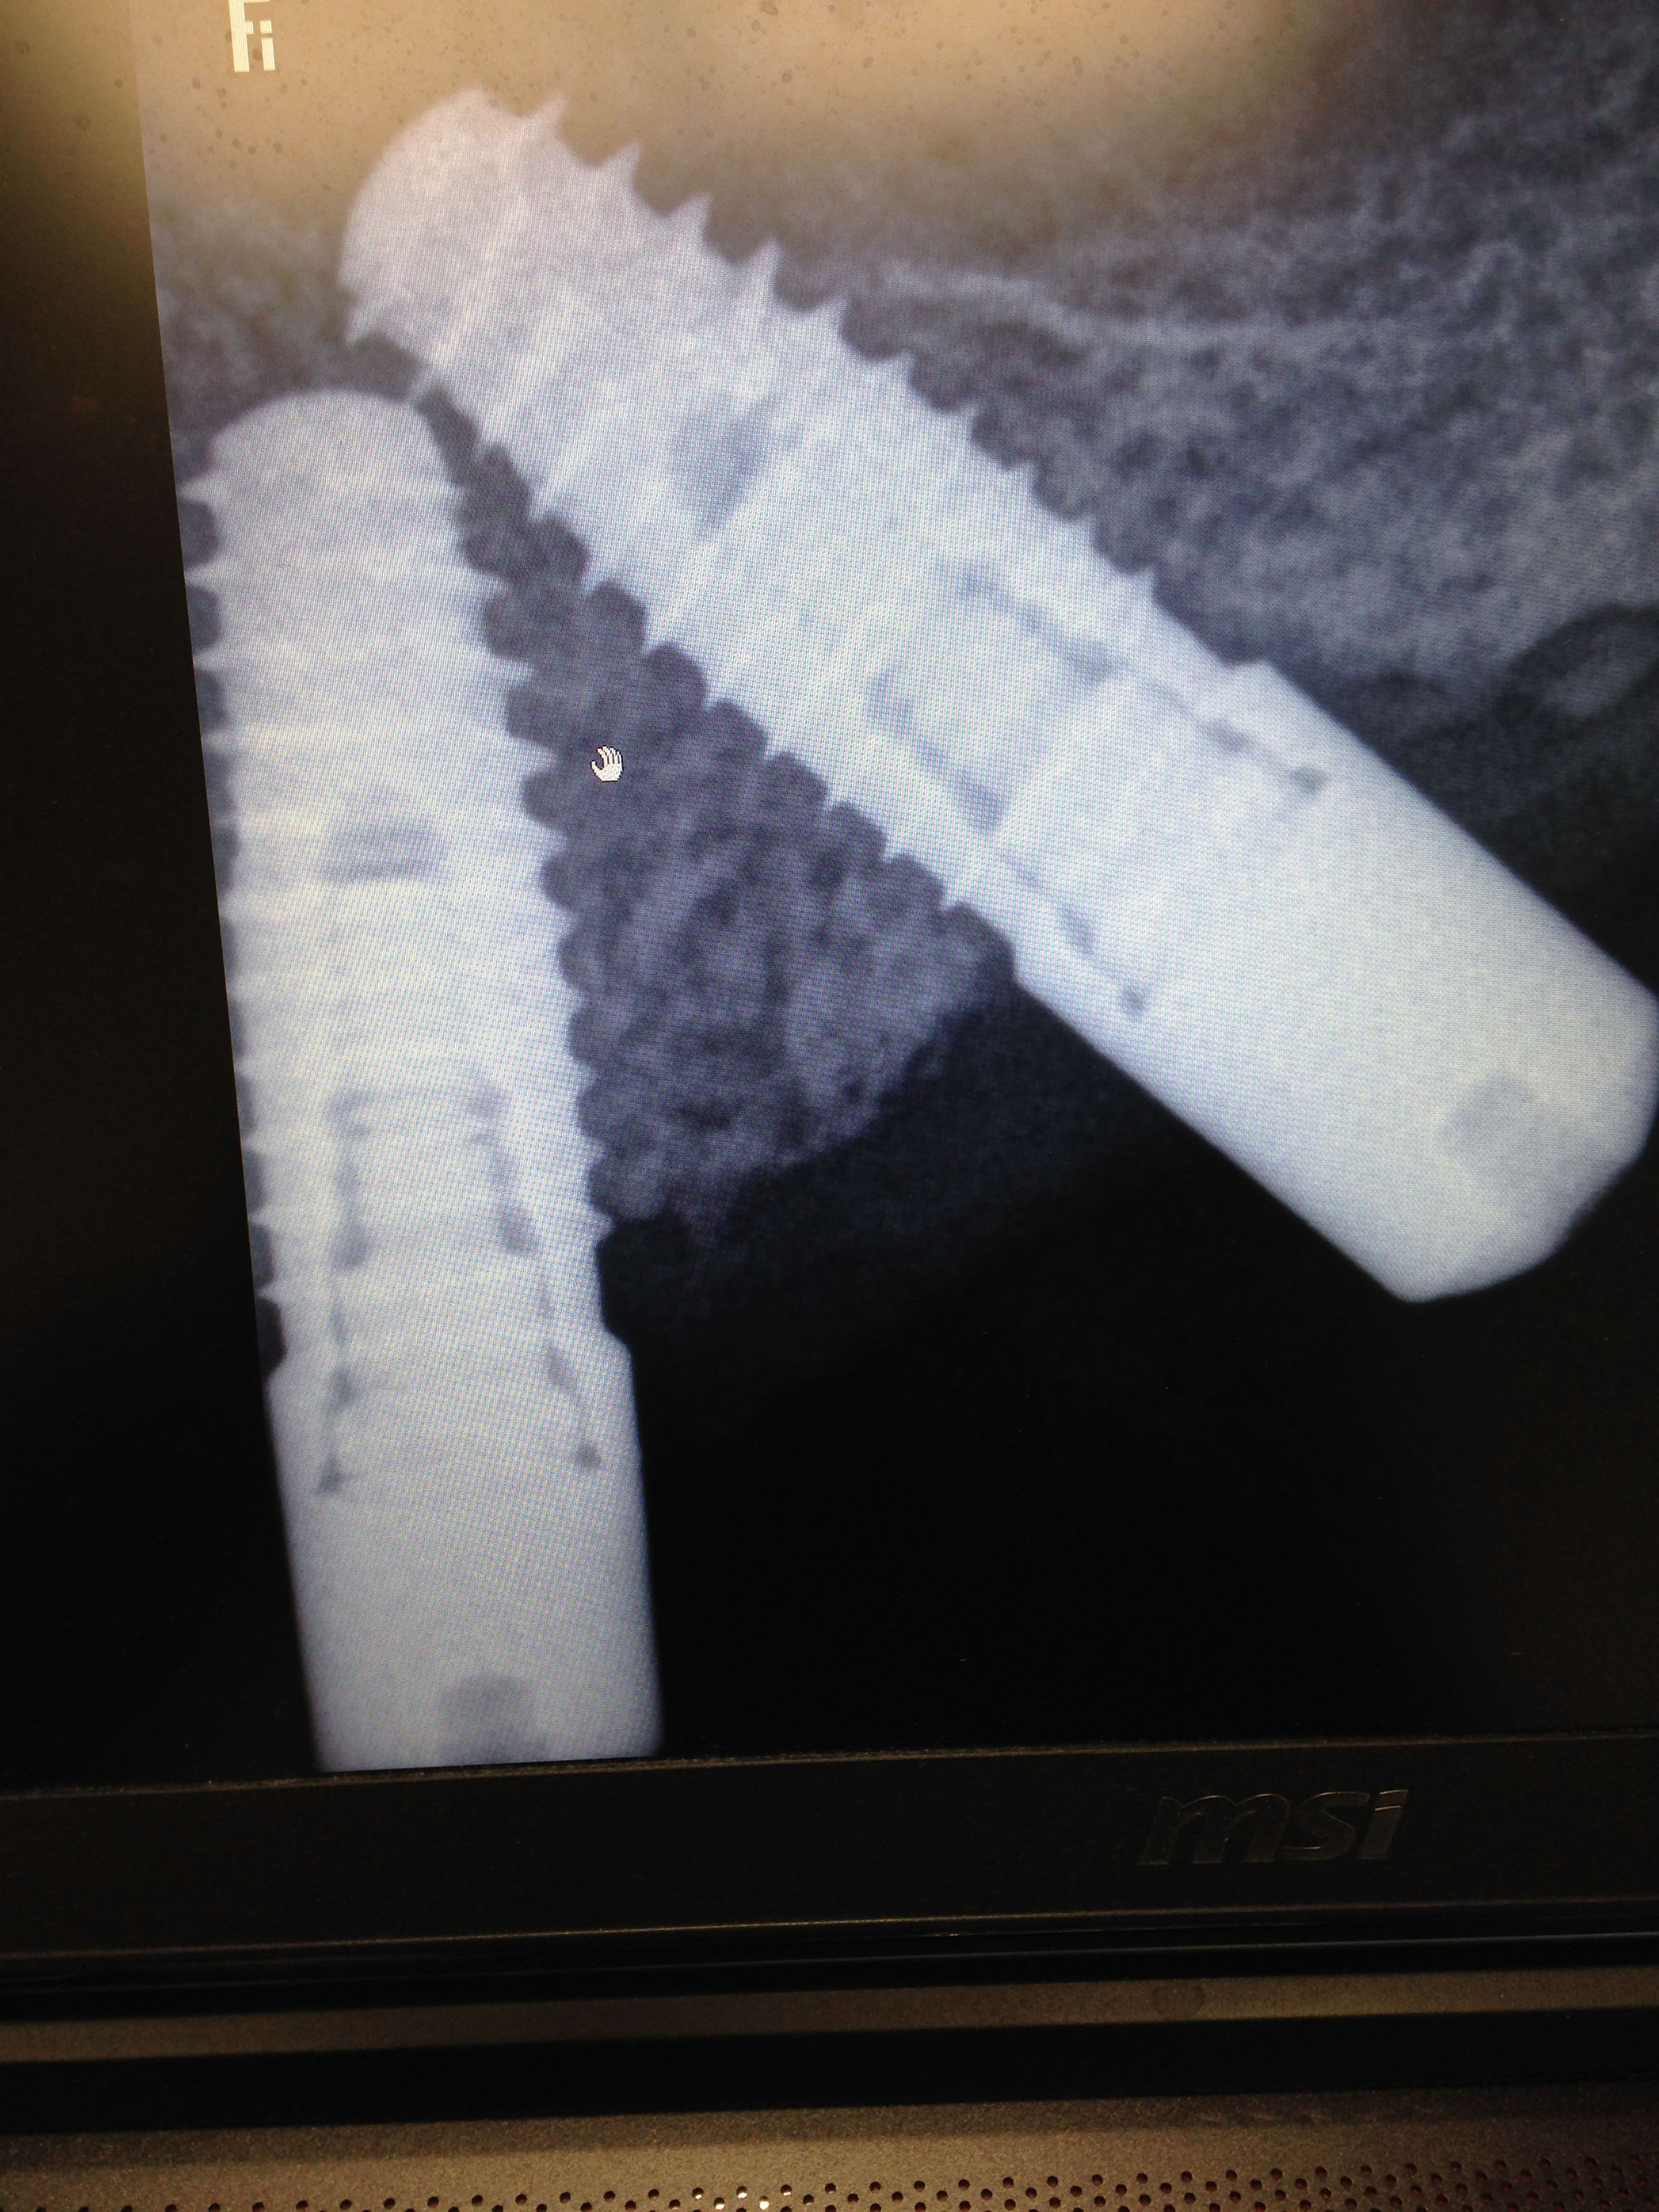

Biomet 3i Nanotite Tapered certain preval

http://whatimplantisthat.com/implant/nanotite-tapered-certain-prevail/

c'est Zimmer/biomet maintenant...

si tu dois faire la prothèse, attend d'avoir le listing de prix et catalogue avant de te lancer dans le devis...sur ce système, la moindre vis coûte un bras...